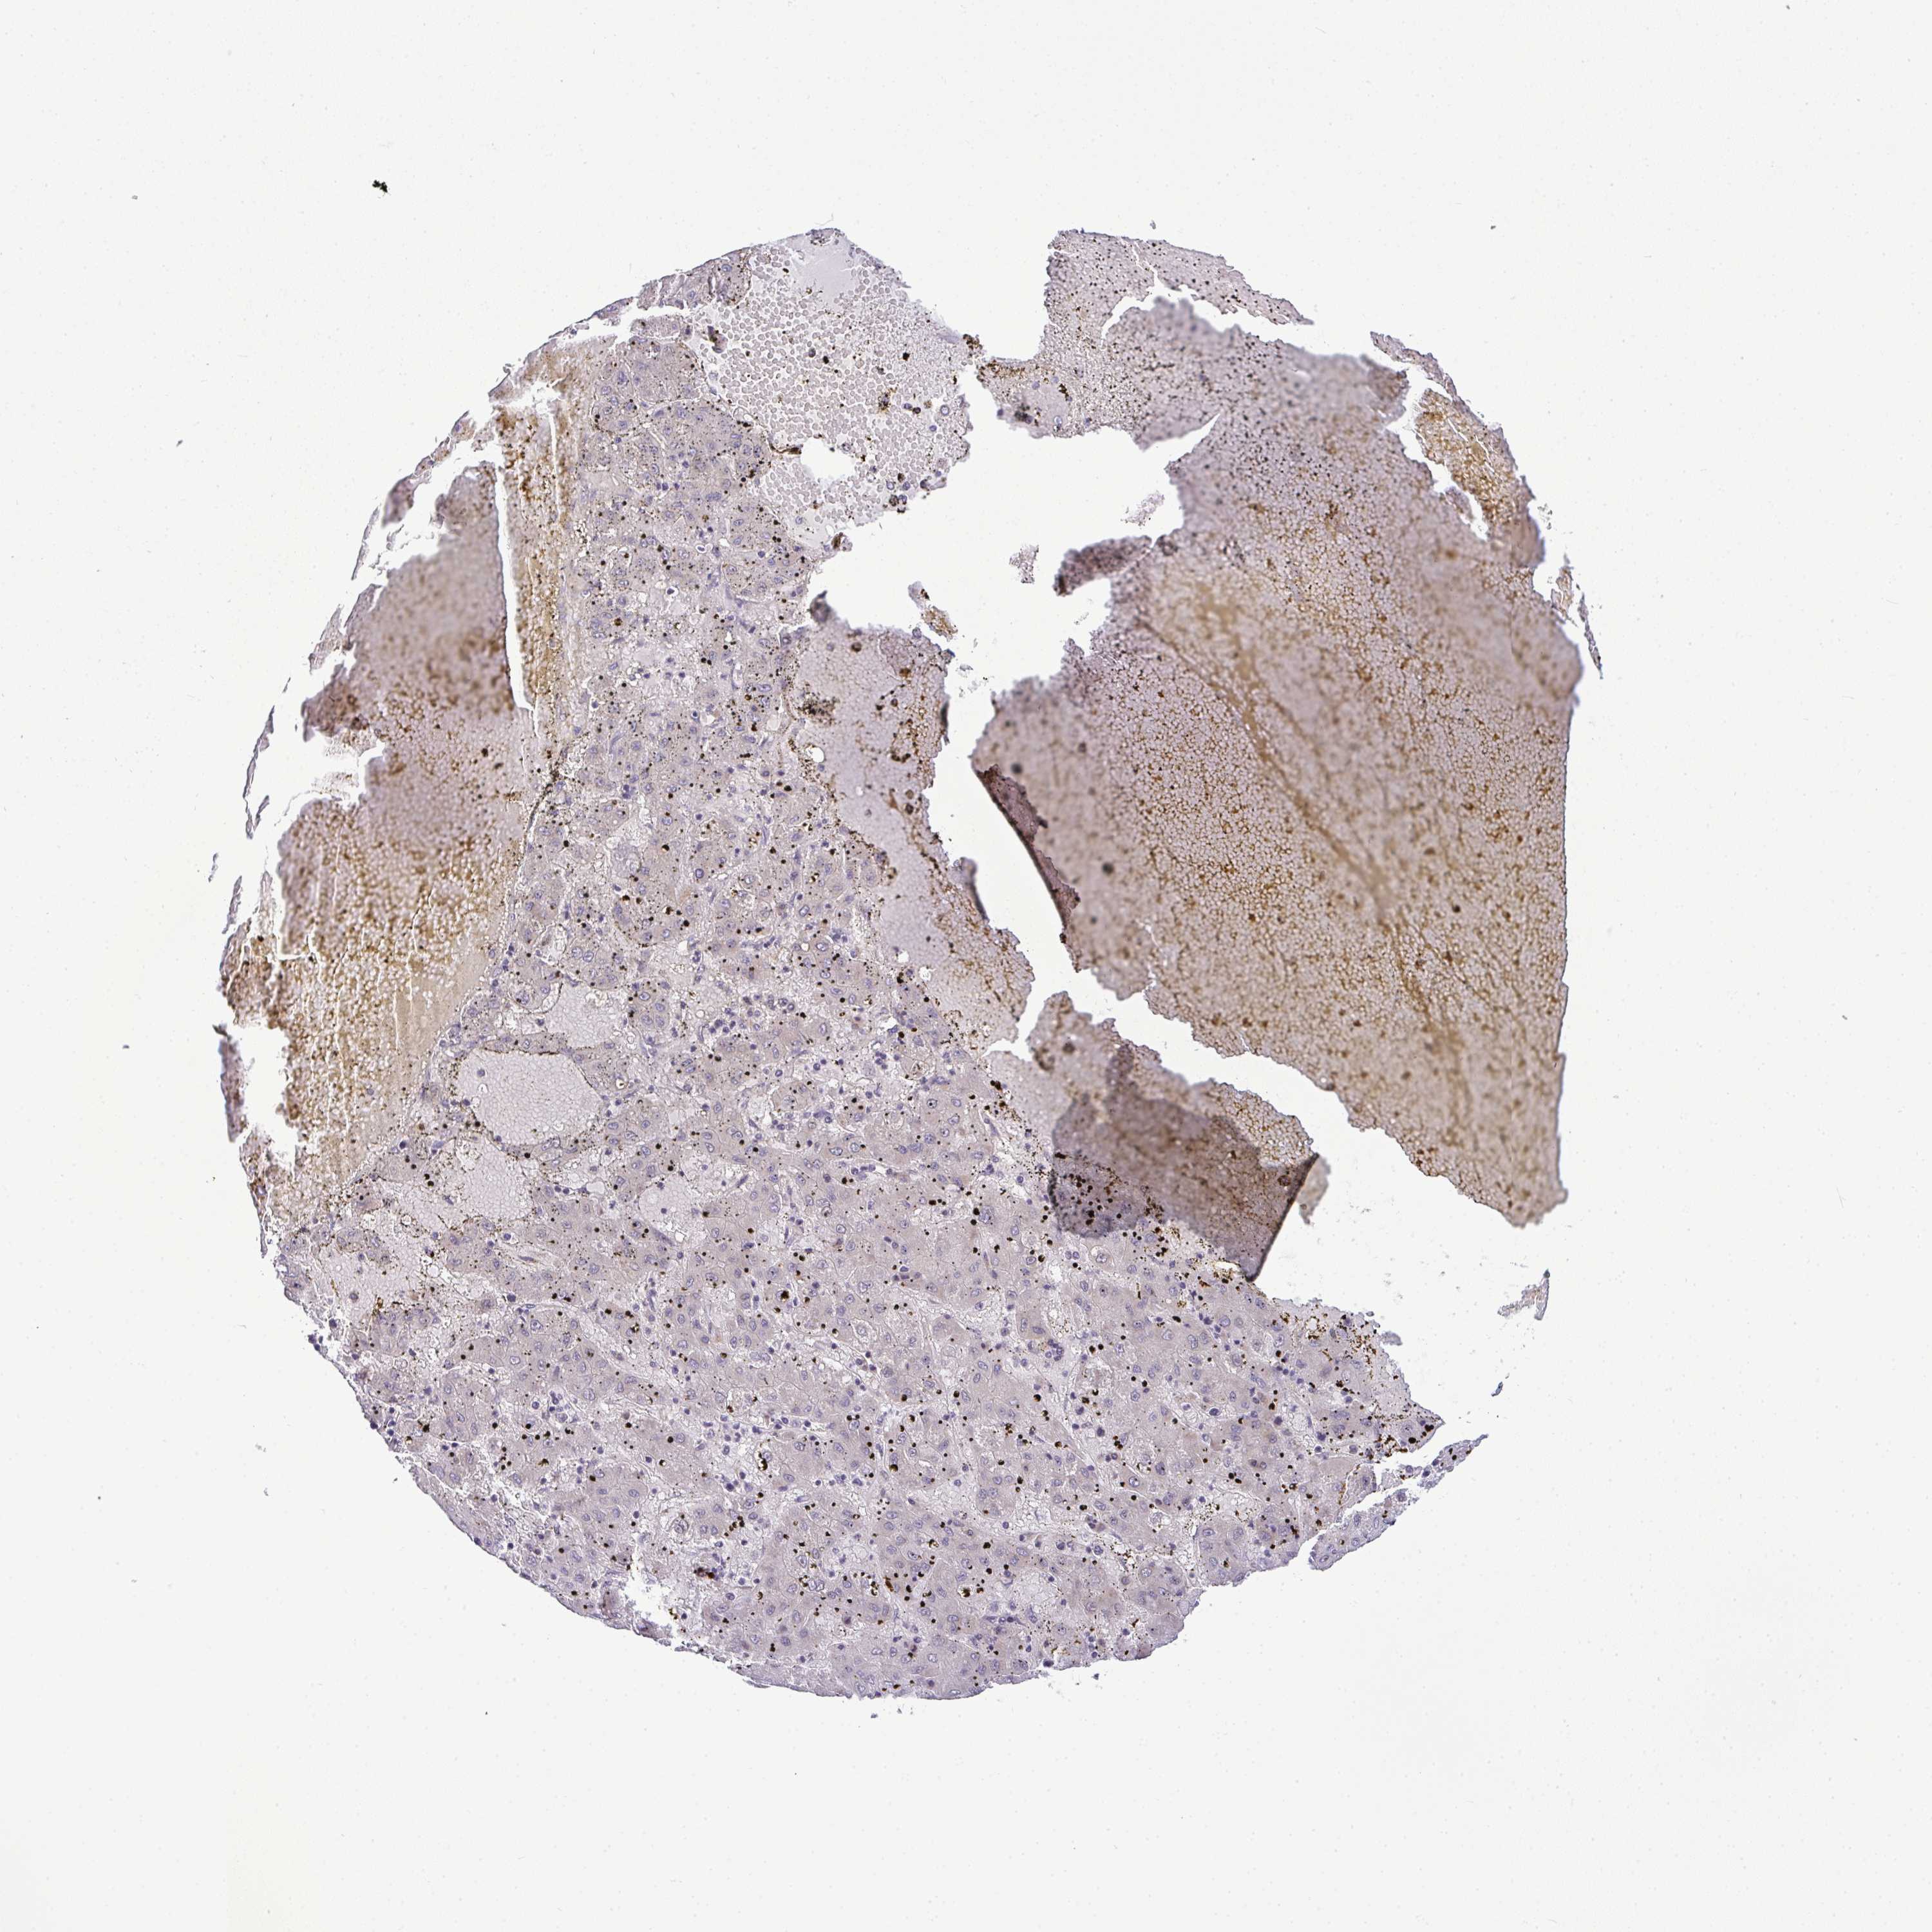

LIVER CANCER - Protein expressioni

A mouse-over function shows sample information and annotation data. Click on an image to view it in a full screen mode. Samples can be filtered based on level of antibody staining by selecting one or several of the following categories: high, medium, low and not detected. The assay and annotation is described here.

Note that samples used for immunohistochemistry by the Human Protein Atlas do not correspond to samples in the TCGA dataset.

Antibody stainingi

Antibody staining in the annotated cell types in the current human tissue is reported as not detected, low, medium, or high, based on conventional immunohistochemistry profiling in selected tissues. This score is based on the combination of the staining intensity and fraction of stained cells.

Each image is clickable and will lead to virtual microscopy that enables deeper exploration of all samples and also displays staining intensity scores, fraction scores and subcellular localization as well as patient and tissue information for each sample.

Antibody HPA050283

Staining

High

Medium

Low

Not detected

Intensity

Strong

Moderate

Weak

Negative

Quantity

>75%

75%-25%

<25%

None

Location

Nuclear

Cytoplasmic/membranous

Cytoplasmic/membranous,nuclear

Carcinoma, Hepatocellular, NOS